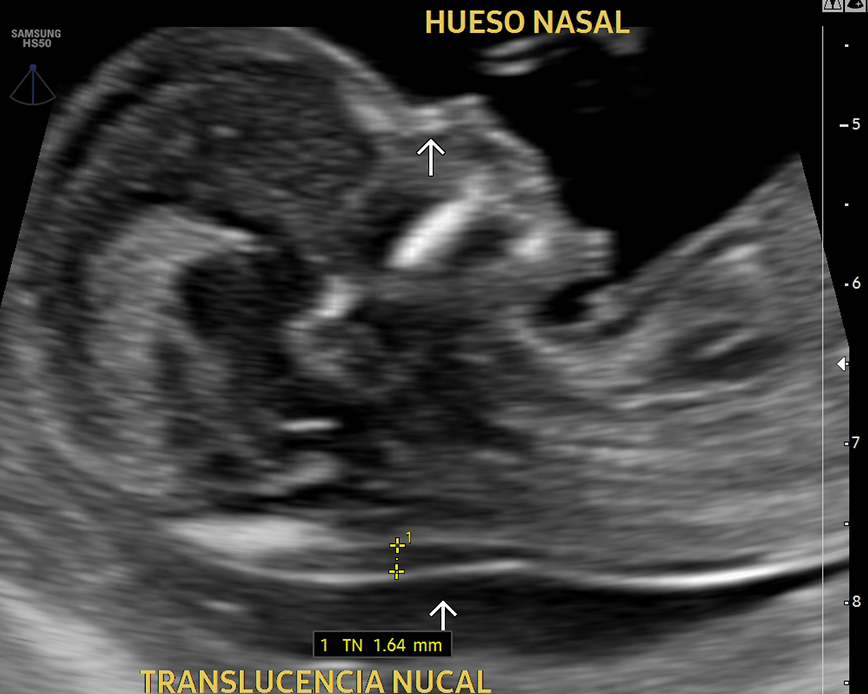

Esta ecografía sirve para evaluar la hemodinamia materno-fetal y detectar problemas de crecimiento como el RCIU (Restricción del Crecimiento Intrauterino) y el riesgo de preeclampsia (presión arterial alta durante el embarazo). Además, nos permite evaluar el cordón umbilical y detectar circulares de cordón simple, doble o triple.